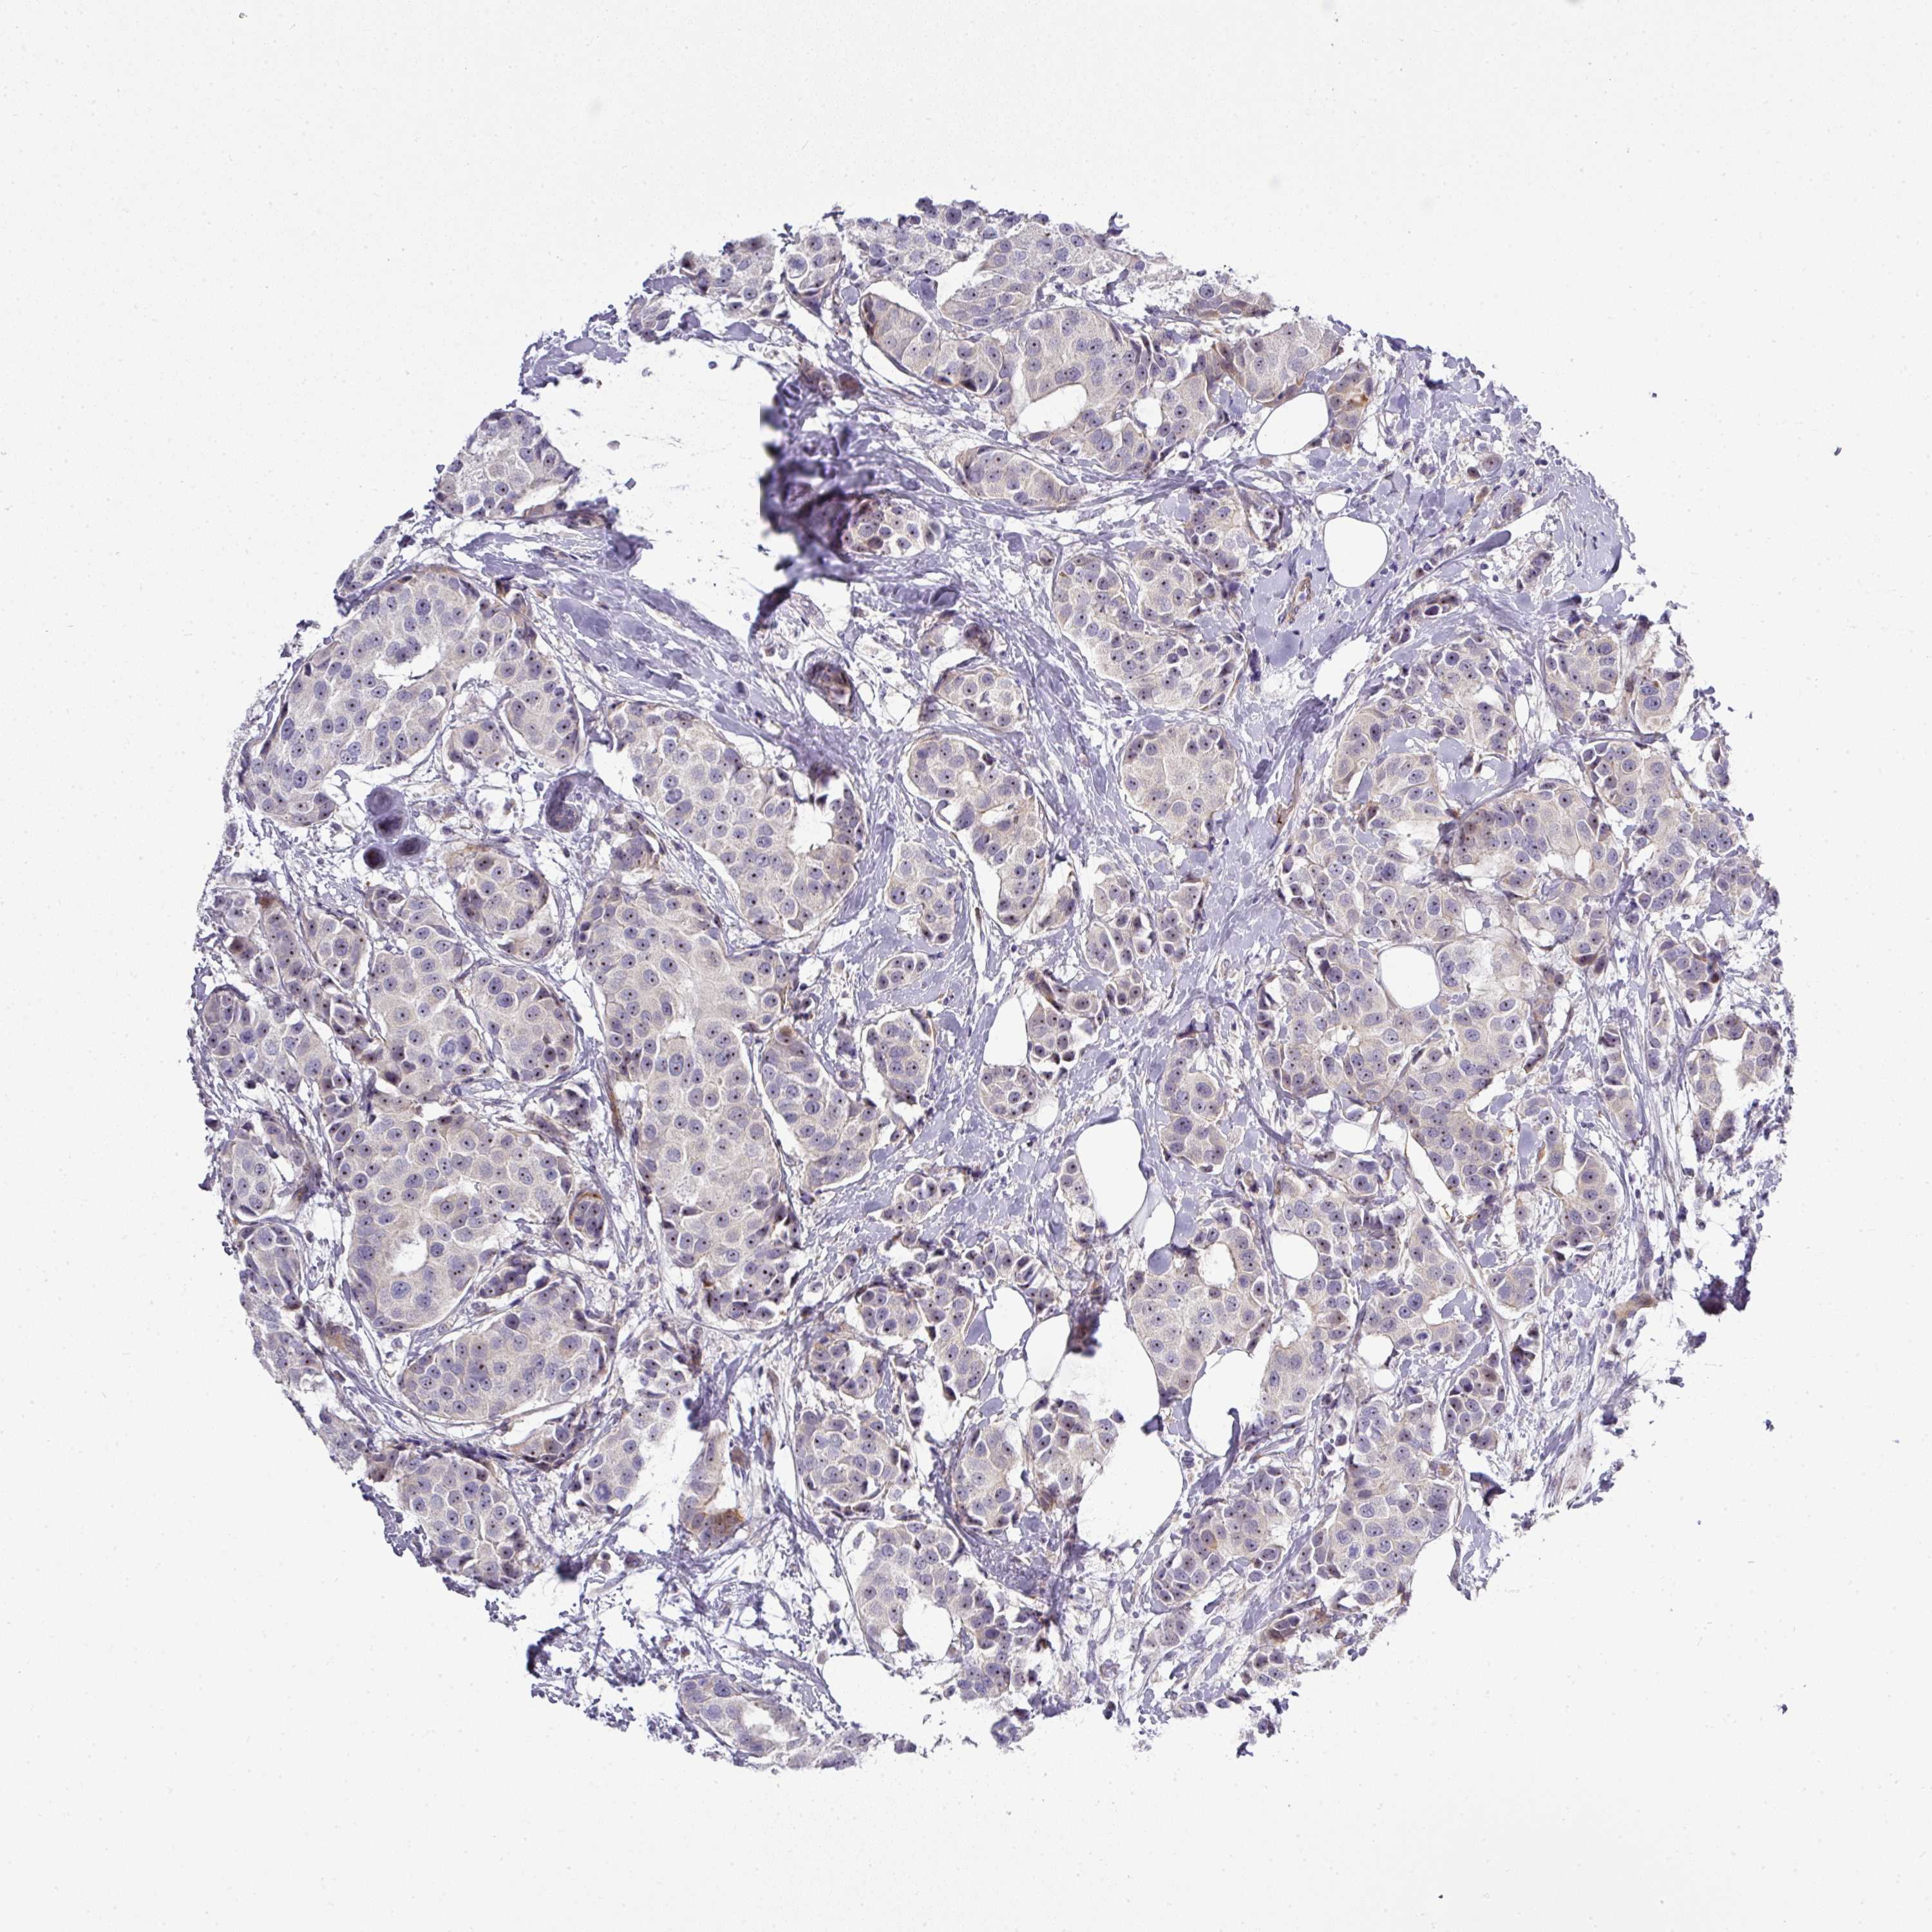

BRCA TCGA BRCA VALIDATION PROTEIN EXPRESSION